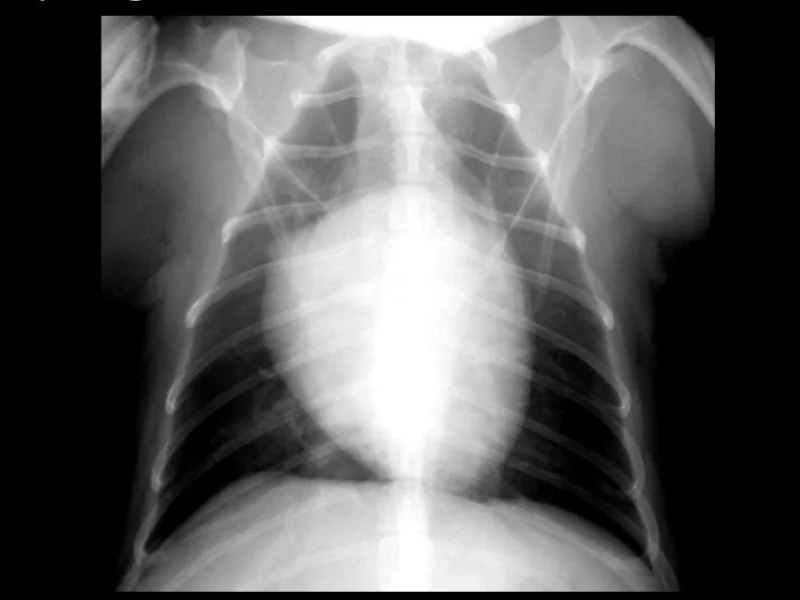

Radiography Interpretation

Expert review and interpretation of thoracic radiographs with a focus on cardiovascular and related findings.